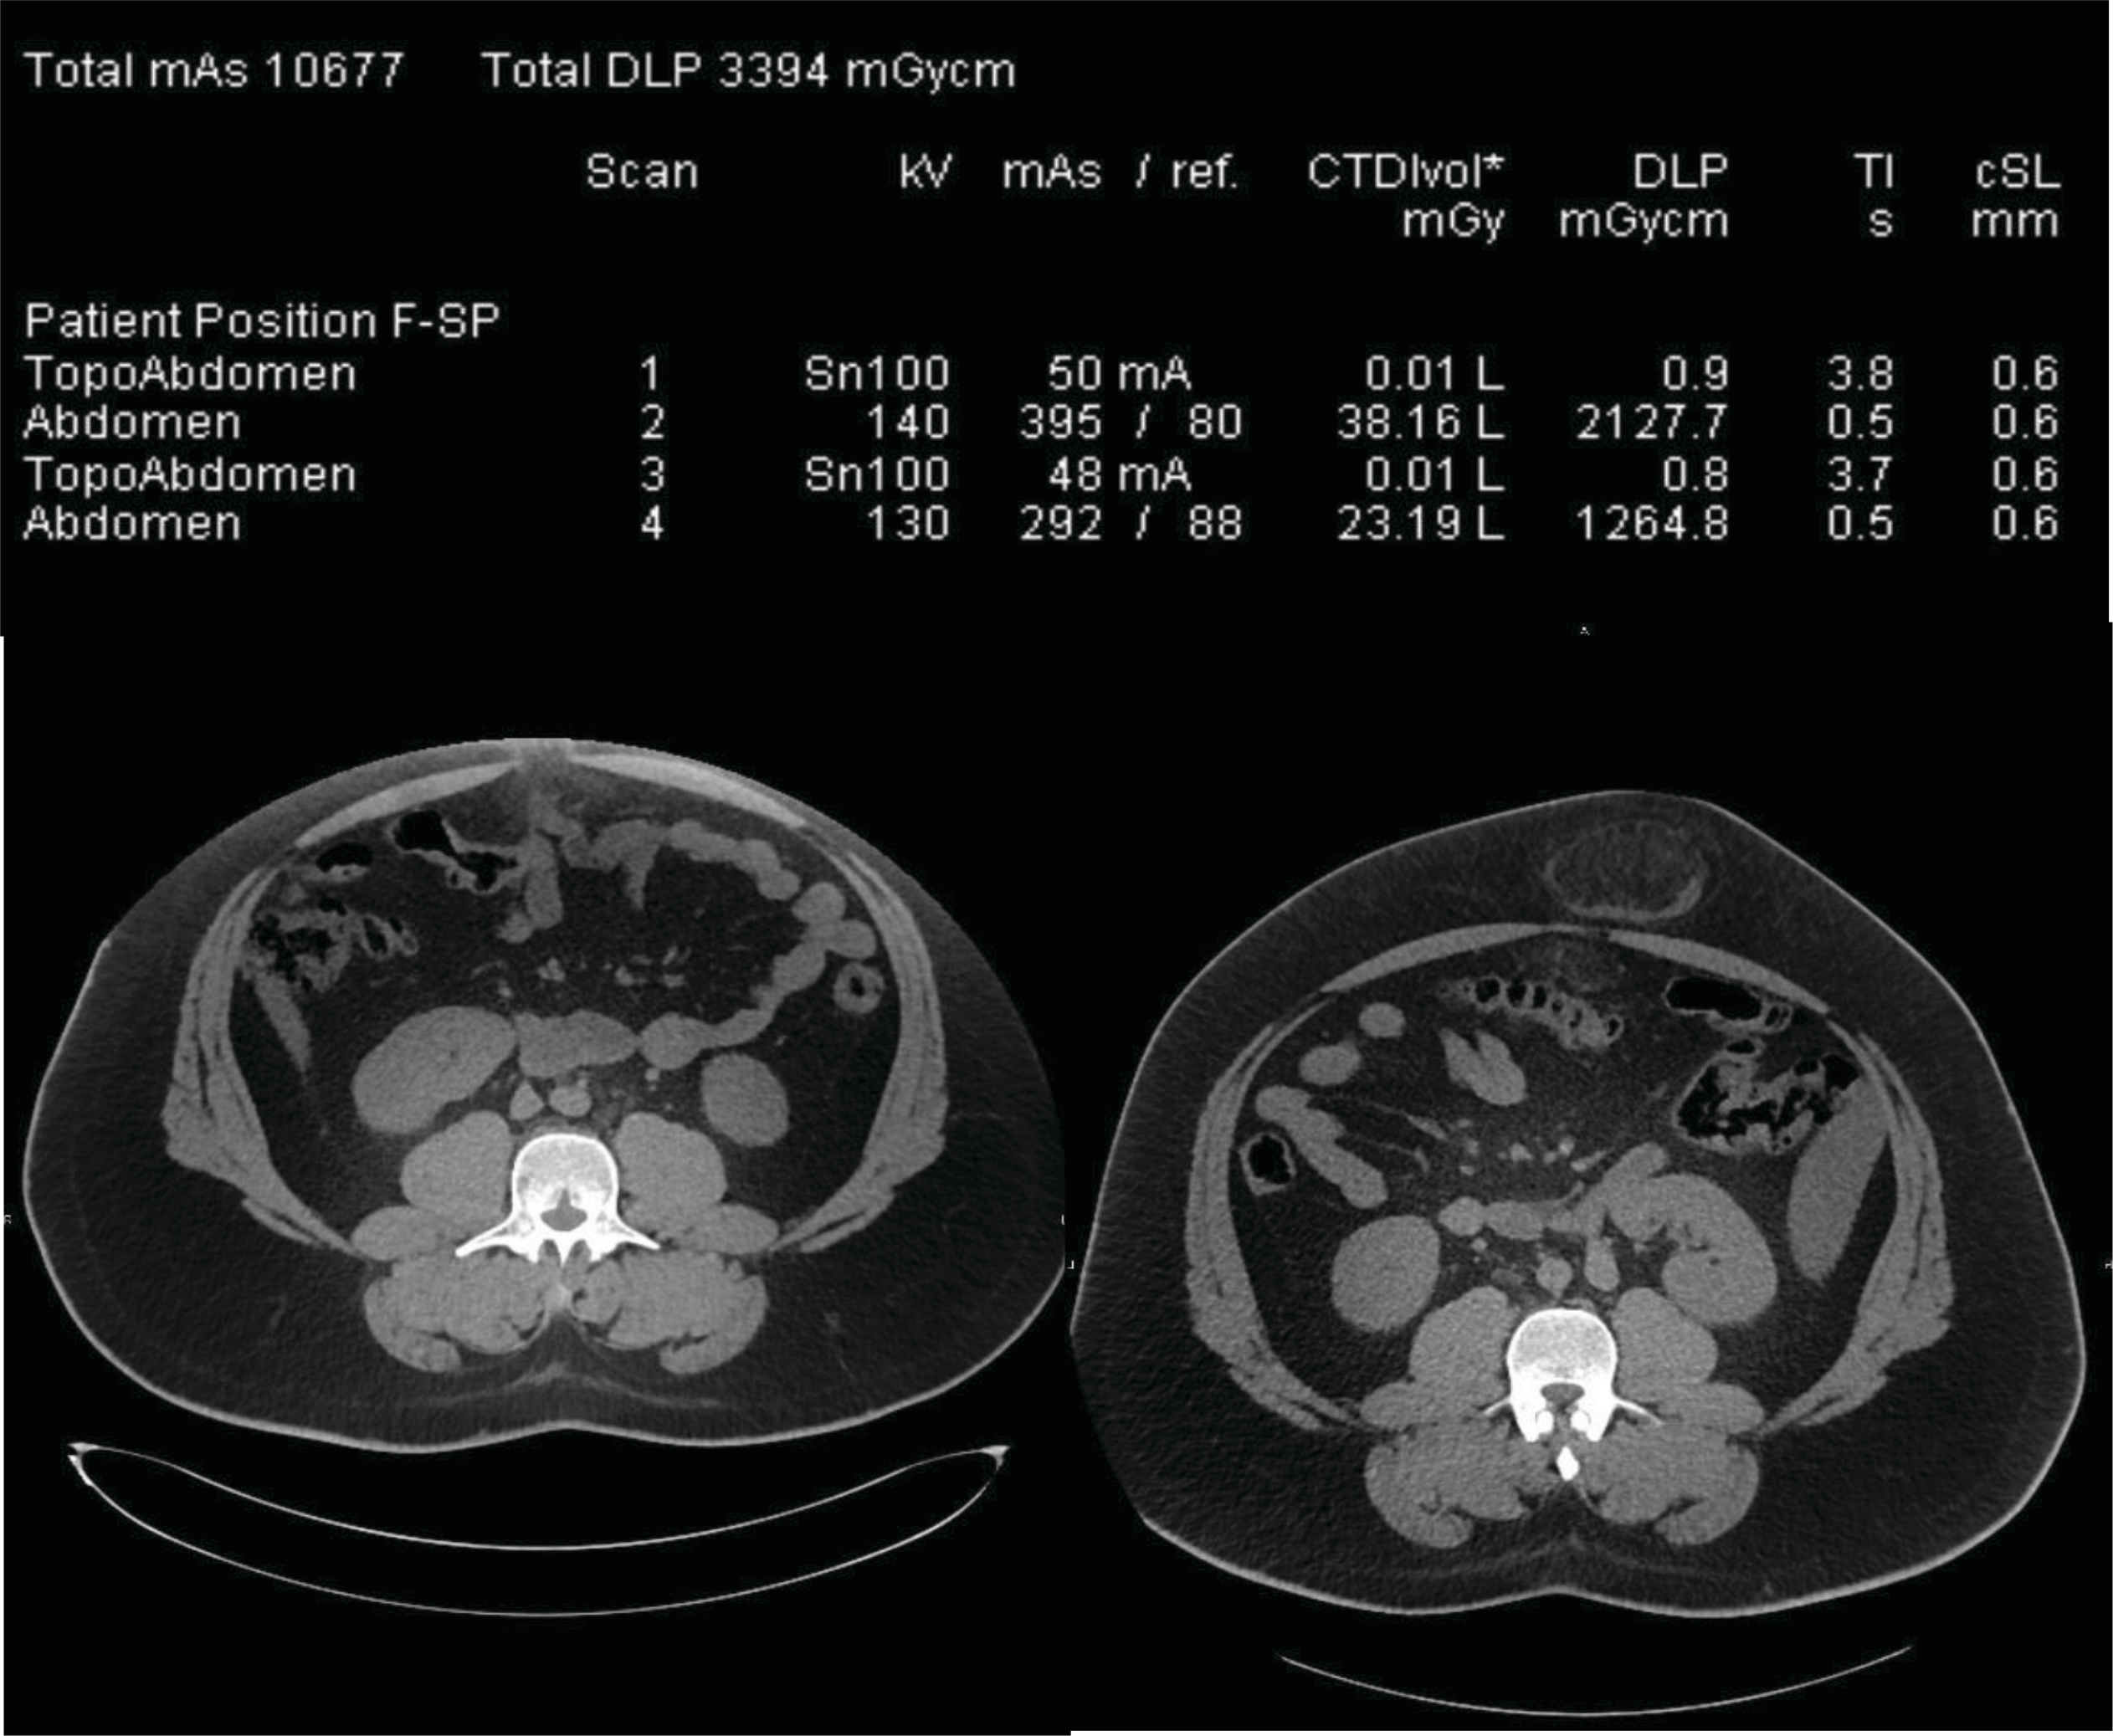

Figure 1 illustrates an off‑centering with a table height set too high: the patient’s effective diameter is 37 cm. He is referred to CT after an inconclusive ultrasound examination of the umbilic and is suspected of umbilical herniation. After an antero‑posterior topogram (first ‘topoAbdomen’ line of the dose report of Figure 1), the planned acquisition of the entire abdomen is obtained (first ‘Abdomen’ line of the dose report).

Figure 1

Radiation dose report and CT slices obtained at the level of the umbilic in a 24 year‑old patient. The left CT slice is off‑centered and the herniation is not visible whereby the right CT slice of correctly centered and the herniation is visible. The two first exposures on the dose report correspond to the left image whereby the two last lines correspond to the right image including the umbilical herniation.

The left CT slice in Figure 1 shows that the umbilical herniation is not included in the image because it is located outside the largest available field of view. Subsequently, the radiologist asked for a repeated acquisition after the patient had been removed from the table. Therefore, the second part of the examination included both the topogram and the helical acquisitions (third and fourth exposure lines on the dose report). The patient centering was modified for the second helical acquisition and enabled to provide images that included the herniation.

The radiation dose report analysis is of interest because it shows that the anterior patient off‑centering during the first acquisition induced a 40% CTDIvol increase (38.16 mGy in comparison to 23.19 mGy) as compared to the second acquisition. This dose increase can be explained by the artificial geometric increase in size of the patient placed too proximal to the detectors during the scout view and interpreted by the AEC as a larger object, thus to be scanned with an increased radiation dose [2, 3].

The total exposure delivered during the examination expressed in dose‑length product (DLP) was 3394 mGy.cm, and corresponded to an effective dose of 51 mSv (conversion factor for CT of the abdomen: 0.015 mSv/mGy.cm). This is clearly an outlier and was thus depicted by our DACS (Intuitus, Telemis, Belgium) that sent an e‑mail alert to the quality officer of the department.